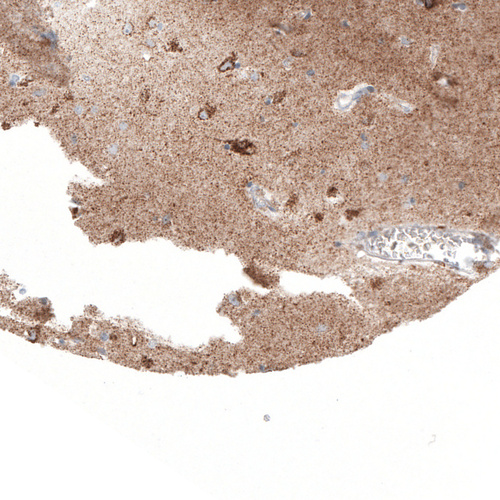

Immunohistochemical staining of human granular layer of the cerebellum shows strong granular cytoplasmic positivity.